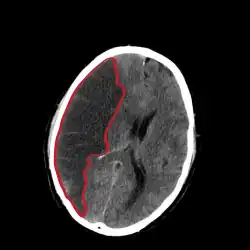

Als Mediainfarkt wird eine besonders lokalisierte Form des ischämischen Schlaganfalls (Hirninfarkt) bezeichnet. Der Ausdruck bezieht sich auf einen Verschluss eines der Hauptgefäße im Gehirn, der Arteria cerebri media („mittlere Gehirnarterie“). Etwa 50 % der Hirninfarkte liegen im Versorgungsgebiet der Arteria cerebri media.[1]

Es wird grob zwischen komplettem Mediainfarkt und Mediateilinfarkt unterschieden. Eine Sonderform ist der maligne Mediainfarkt, der aus großen Mediainfarkten entstehen kann. Er ist gekennzeichnet durch eine lebensgefährliche Hirndrucksteigerung, die durch das 2–5 Tage nach Infarktereignis entstehende Infarktödem verursacht wird.

Nach Ausschluss einer Blutung mittels Computertomographie und Ausschluss anderer Kontraindikationen wird eine zügige Lysetherapie angestrebt, wenn das Zeitintervall zwischen Symptombeginn und Therapiebeginn nicht länger als 4,5 Stunden ist. Prinzipiell sollte der Patient einer möglichst schnellen Behandlung in einem Krankenhaus mit Stroke Unit zugeführt werden. Es gibt darüber hinaus die Möglichkeit, einen Hirninfarkt mittels eines interventionellen Verfahrens zu therapieren.